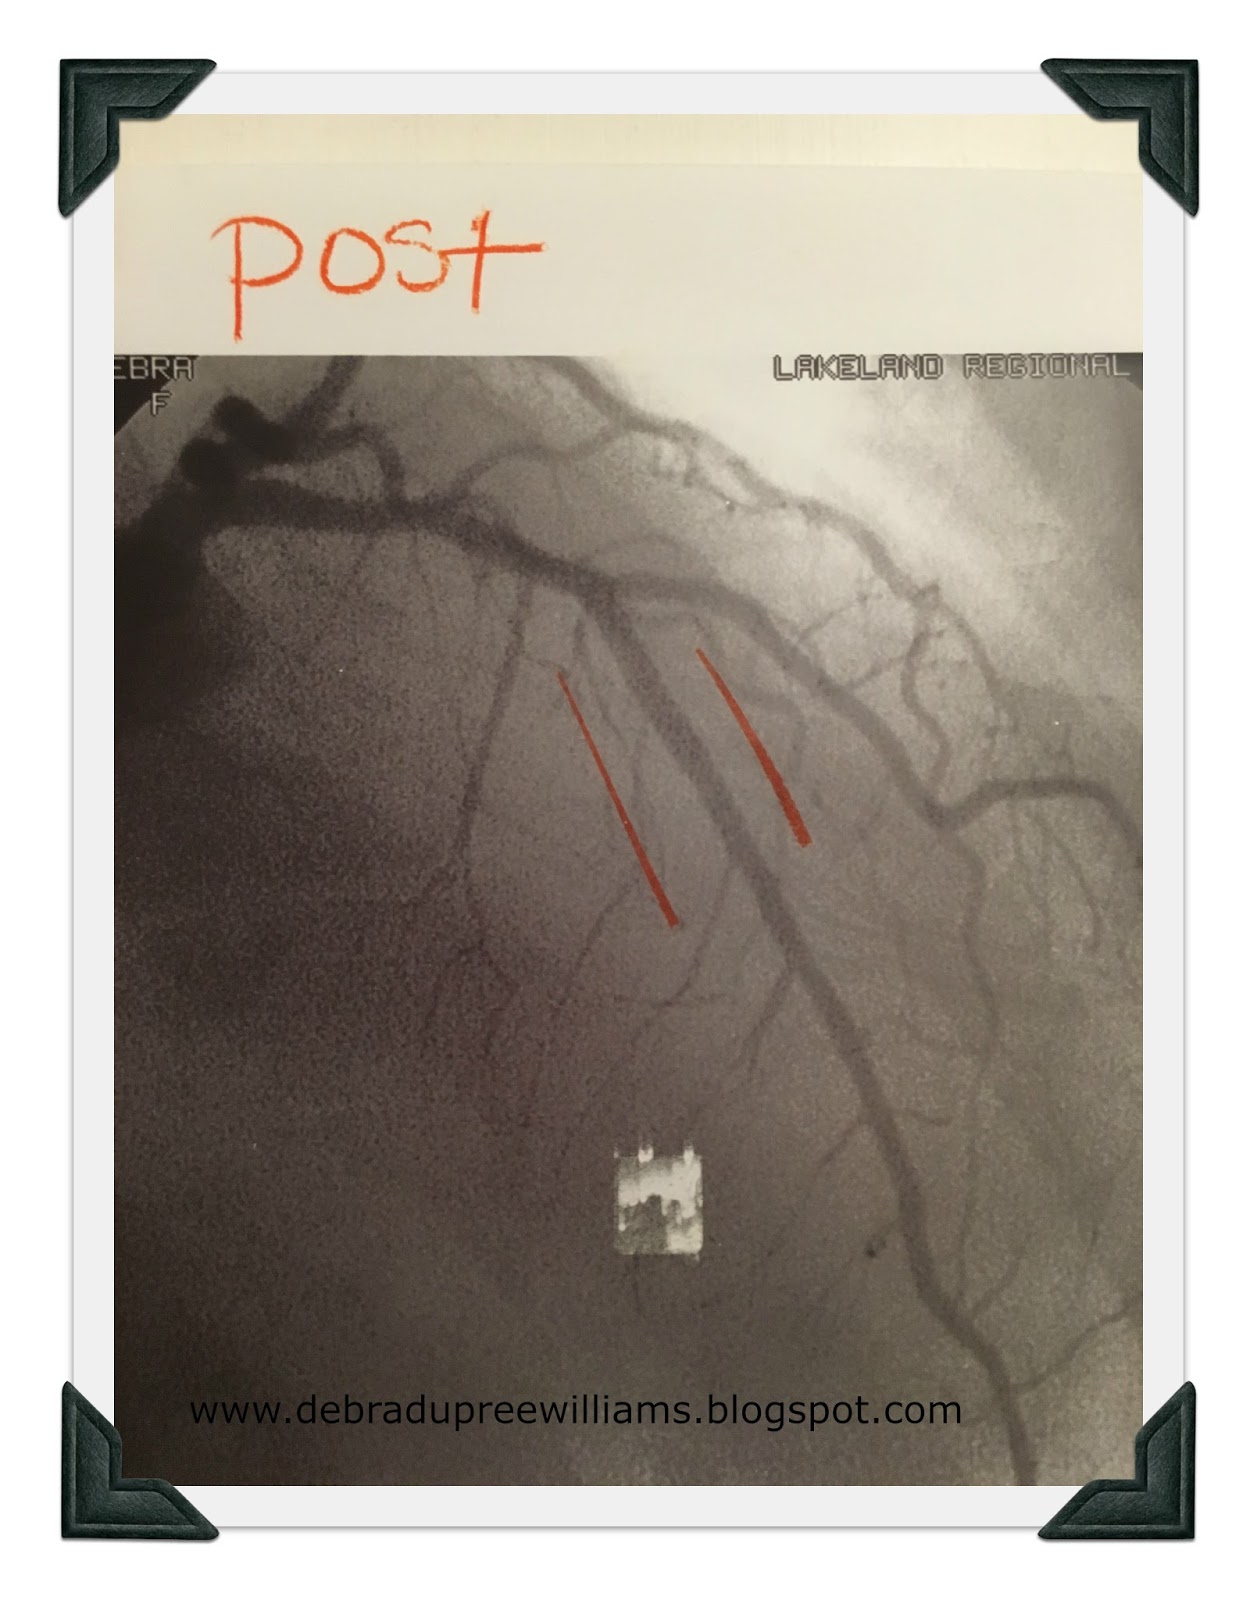

After I had received the stent and recovered sufficiently for the doctor to talk to us, he showed us before and after x-rays. By the grace of God alone, I had a tiny little blood vessel that had formed its own bypass around the clogged artery, the main one on the front of the heart, the Left Anterior Descending, the LAD, also known as the widow-maker. It was 99.9% blocked. But I was still alive!